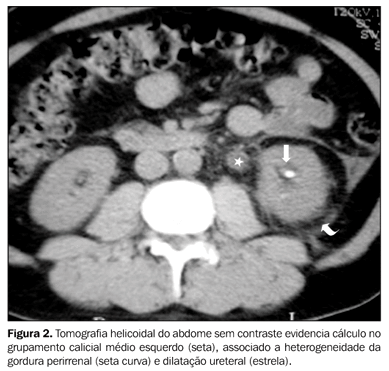

Qual o exame padrão-ouro para o diagnóstico de Nefrolitíase?

TC de vias urinárias sem contraste